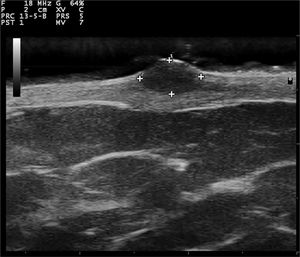

Gray-scale and color Doppler US examinations of both the subcutaneous nodule and one of the papules located on the right periareolar region (Fig. 1) were performed with a MyLab25Gold scanner equipped with a 10–18 MHz linear array transducer (Esaote, Genoa, Italy). High-frequency US of the subcutaneous malar nodule revealed an ill-defined, elongated, heterogeneous, and hypoechoic mass located in the deep dermis and hypodermis (Fig. 2). On the other hand, the US of the right periareolar papule showed a well-defined, round, homogeneous, and hypoechoic lesion located in the superficial dermis with an elevation of the epidermis (Fig. 3). Color and directional power Doppler US showed no increased vascularity in neither of the two lesions. Surgical removal and histopathology of two papules on the trunk confirmed the diagnosis of cutaneous myxomas (Fig. 4). The malar lesion was not excised for cosmetic reasons.

While cardiac myxomas sonographically present as pedunculated, atrial, hyperechoic masses; ultrasonography of cutaneous myxomas is yet to be described in the literature. The authors have observed that they show different ecographic features depending on their location in the skin. Superficial myxomas present as well-defined, round, homogeneous, and hypoechoic lesions located in the superficial dermis with an elevation of the epidermis. Instead, subcutaneous myxomas appear as ill-defined, elongated, heterogeneous and hypoechoic masses located in the deep dermis and hypodermis. The sonographic differential diagnosis of superficial myxomas should be made with benign skin tumors such as cysts, dermatofibromas, pilomatrixomas, and neurofibromas. Cysts are well-defined, round, hypoechoic, or anechoic lesions and usually present posterior enhancement and bilateral edge shadowing. Dermatofibromas are ill-defined, hypoechoic and heterogeneous lesions. In the US, pilomatrixomas appear as hypoechoic lesions with well-defined margins and typically present multiple small calcifications and posterior shadowing. Color Doppler US generally reveals a single artery that penetrates the lesion and gives rise to multiple intralesional branches.7 Neurofibromas are round, oval-shaped, or fusiform hypoechoic lesions that can show a connection with hypoechoic neural tracts. On the other hand, the sonographic differential diagnosis of subcutaneous myxomas should be made with deeper lesions like abscesses or lipomas. In the US, abscesses appear as heterogeneous fluid collections with irregular margins and increased vascular flow on Color Doppler US in case of active inflammation. Lipomas are usually ovoid, hypoechoic, subcutaneous masses with linear hyperechoic horizontal lines within the lesion.